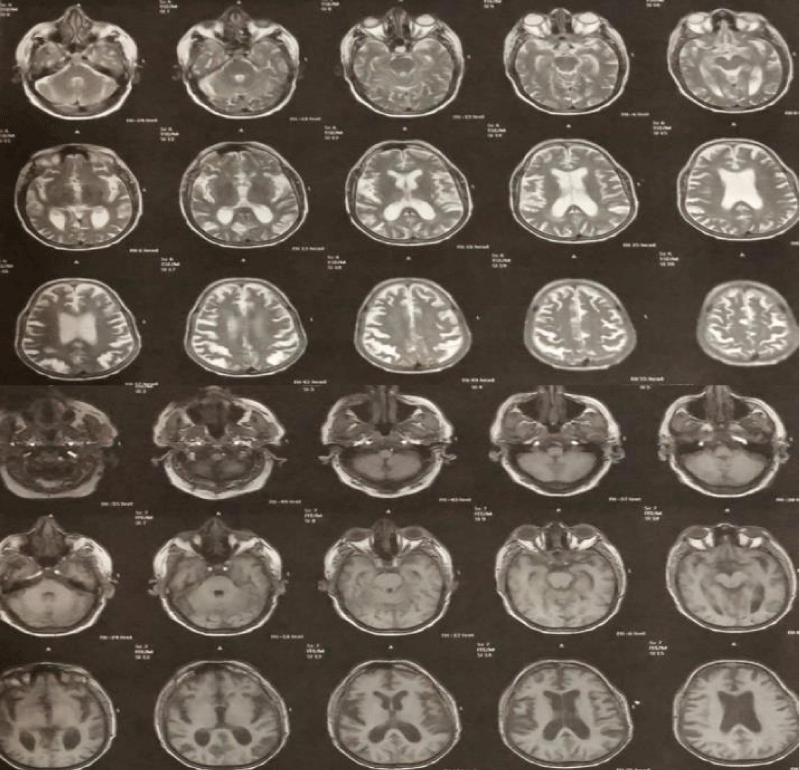

Duplex ultrasound of both legs showed no evidence of deep vein thrombosis, echocardiography showed reserved LV function (ejection fraction 75%), reversed E/A ratio, and mild mitral regurgitation. The right ventricle was normal and no thrombus or effusion was observed. A computerized scan of the brain showed no evidence of cerebral hemorrhage or infarction. MRI of the brain showed mild brain atrophy but no ischemia or hemorrhage (Figure 1).

Figure 1: Normal T1 and T2 magnetic resonance images of the brain.